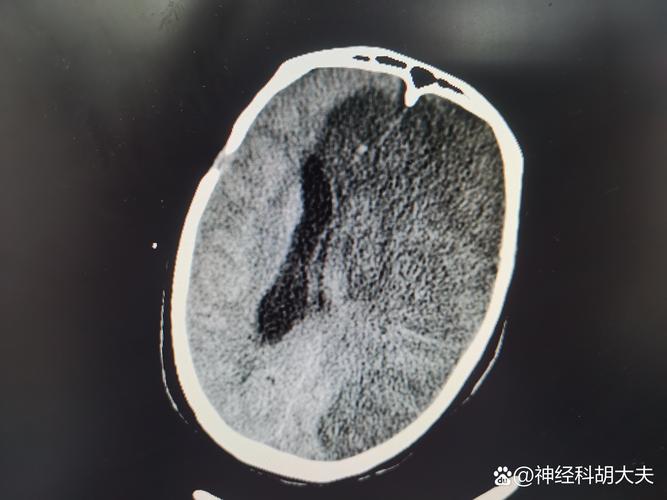

(图片来源网络,侵删)

(图片来源网络,侵删) -